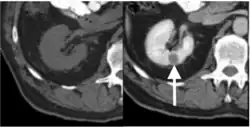

Contrast-enhanced computed tomography (CT) is most commonly used to identify the subtypes of RCC. PRCC can be differentiated from other types of RCC due to its distinguishing features, displaying a small hypovascular renal tumor on T2 weighted images.[7] Typically, PRCC tends to appear homogeneous while clear cell RCC is likely to be in a heterogeneous form when the tumor is less than 3 cm in diameter.[30] Comparatively, in cases of tumors larger than 3 cm in diameter, PRCC is generally heterogeneous with areas of necrosis and hemorrhage compared to chromophobe RCC.[8][31] Solid, small PRCC tumors (<3 cm in diameter) are more easily viewed on nephrographic, excretory phase images rather than on unenhanced, corticomedullary phase images.[8]

Magnetic resonance imaging (MRI)

Magnetic resonance imaging (MRI) is recommended instead of CT for patients with an allergy to iodinated contrast materials.[8] As some renal tumors do not enhance significantly on CT, MRI examination is required to be performed with more sensitive contrast enhancement.[7] On MRI, the distinct features of PRCC are fibrous capsules and homogeneously low single intensity on both T1- and T2-weighted images.[8][32] Specifically, PRCC exhibits hypointensity due to its dense collagenous matrix or deposition of calcium and hemosiderin within the tumor.[33] Such visual features help PRCC to be differentiated from clear cell RCC, which has heterogeneously higher single intensity shown on T2-weighted images.[8][32] PRCC displays the smallest tumor-to-cortex enhancement at corticomedullary and nephrographic phases when juxtaposed with clear cell and chromophobe RCCs.[32]